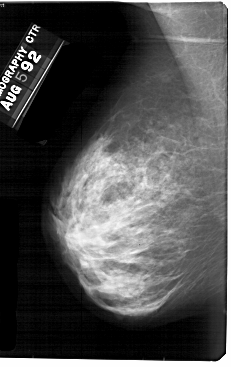

A_1693_1.LEFT_MLO

LEFT_MLO LINES 5491 PIXELS_PER_LINE 3451 BITS_PER_PIXEL 12 RESOLUTION 43.5 NON_OVERLAY